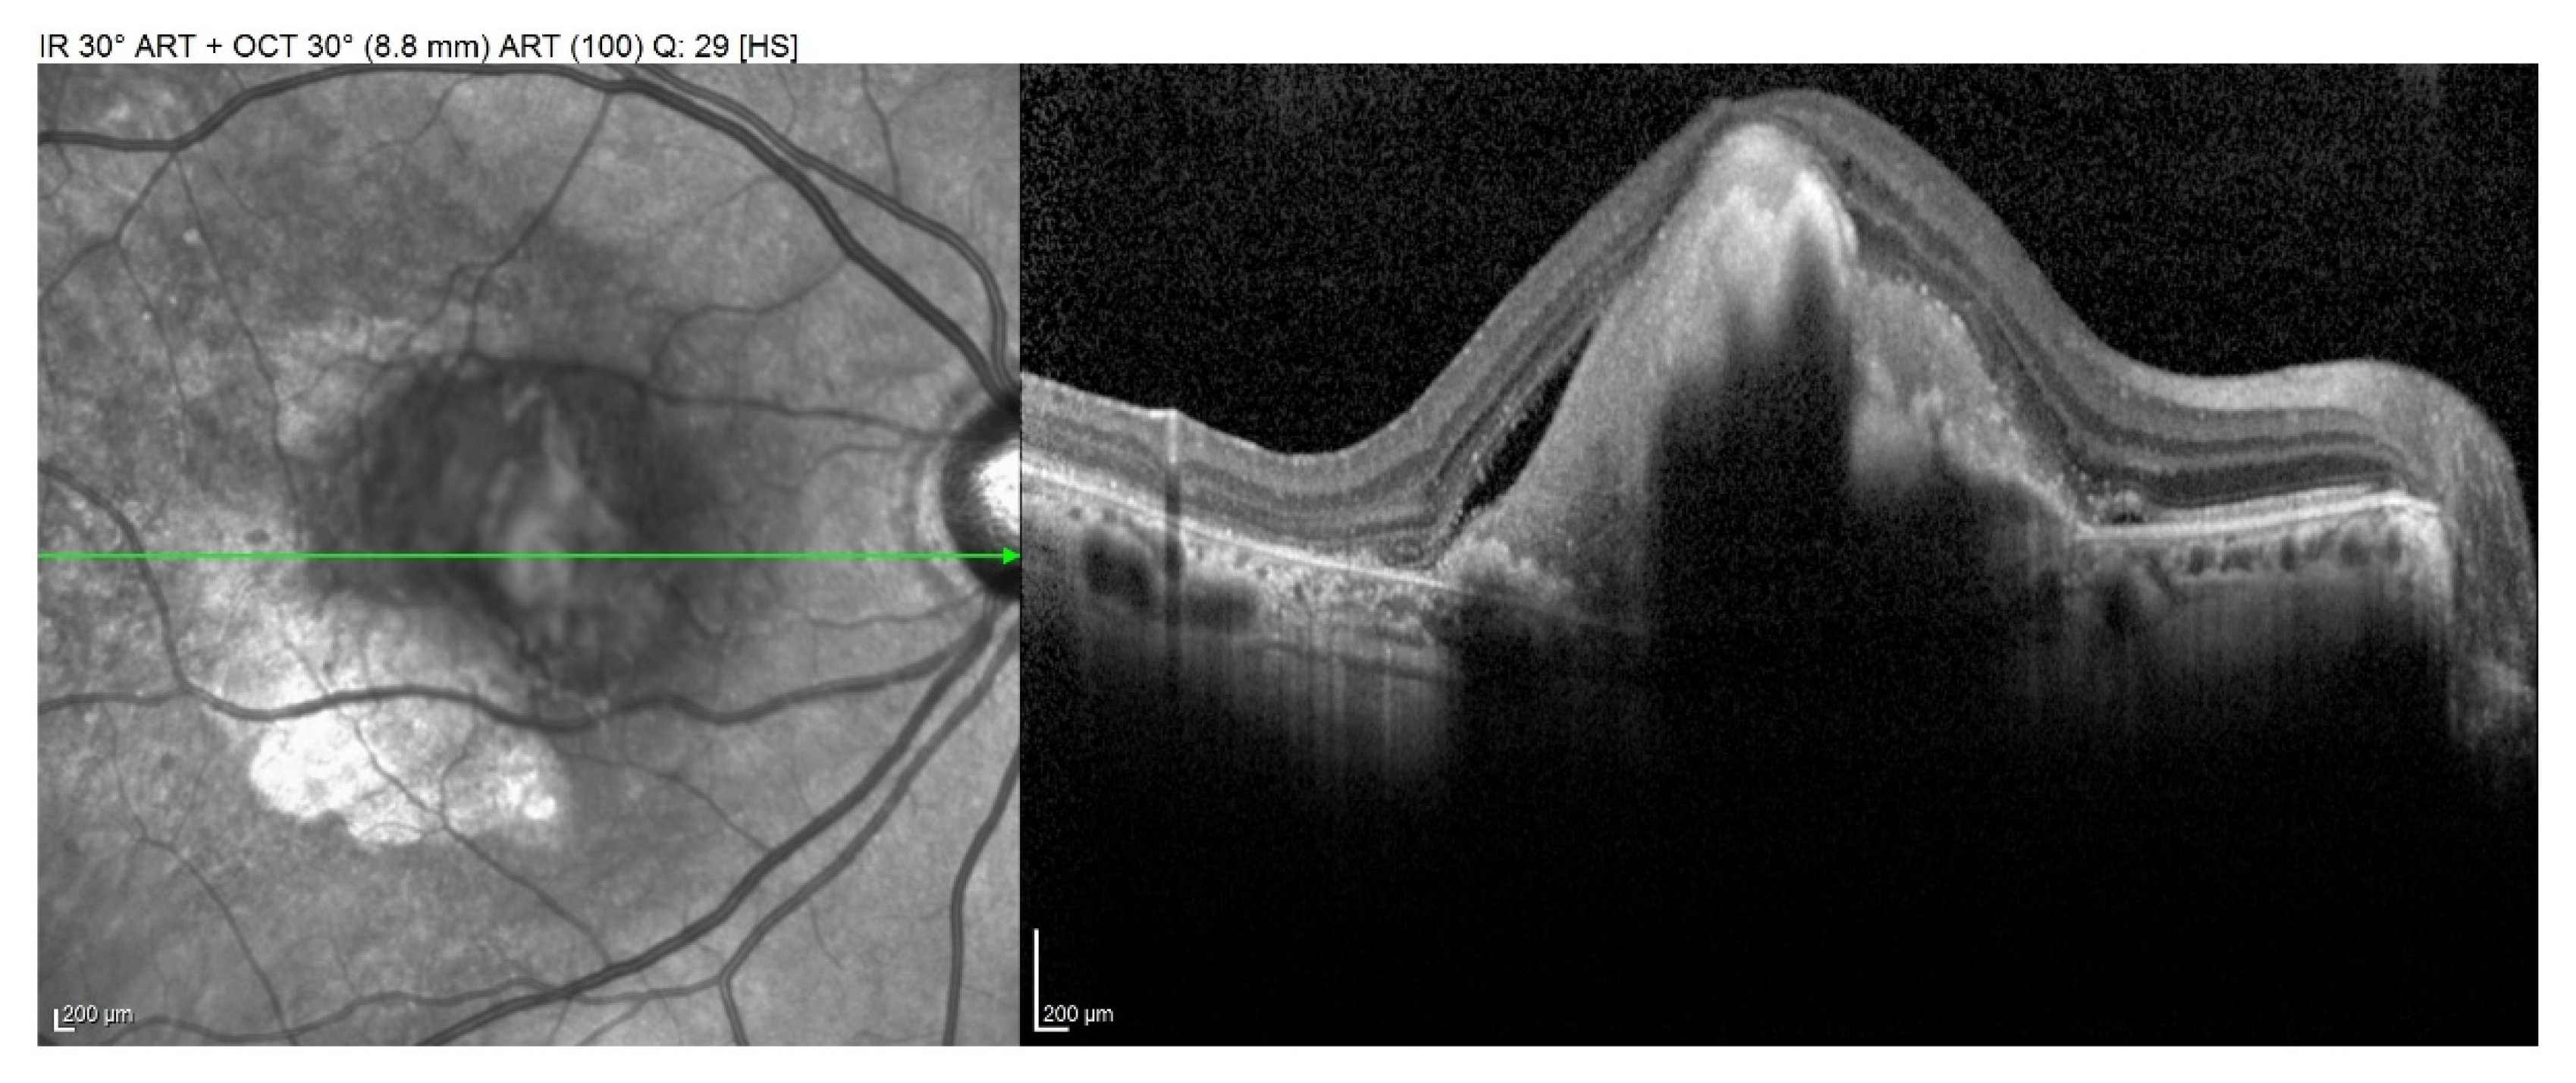

- Gregori, G.; Wang, F.; Rosenfeld, P.J.; Yehoshua, Z.; Gregori, N.Z.; Lujan, B.J.; Puliafito, C.A.; Feuer, W.J. Spectral domain optical coherence tomography imaging of drusen in nonexudative age-related macular degeneration. Ophthalmology 2011, 118, 1373–1379. [Google Scholar] [CrossRef]